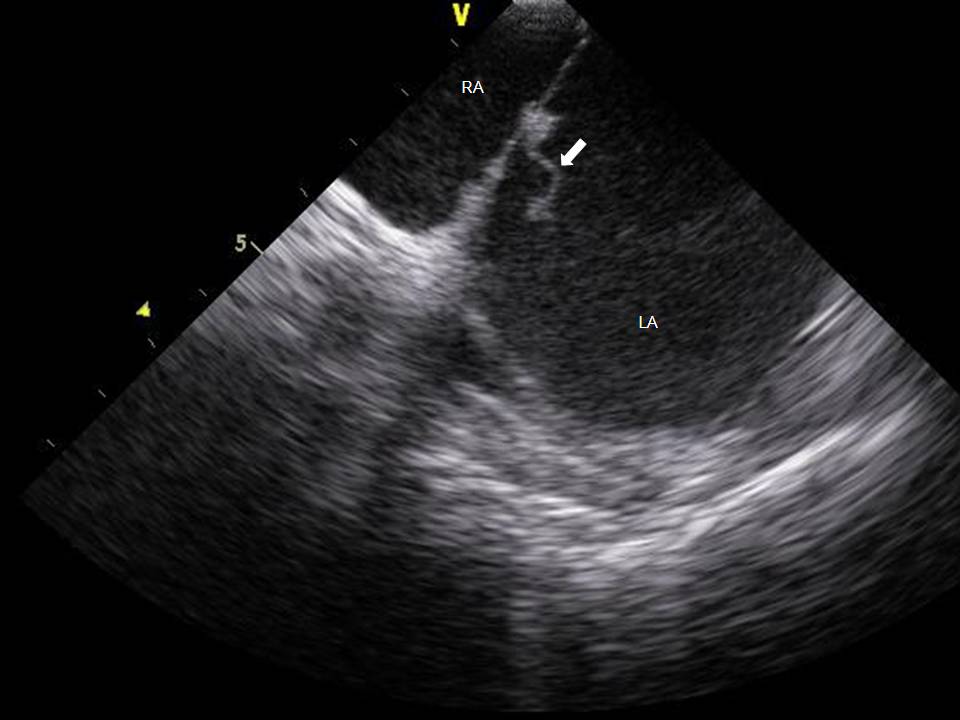

Use of ICE to Eliminate Radiation During AF Ablation

2015-07-24 13:06